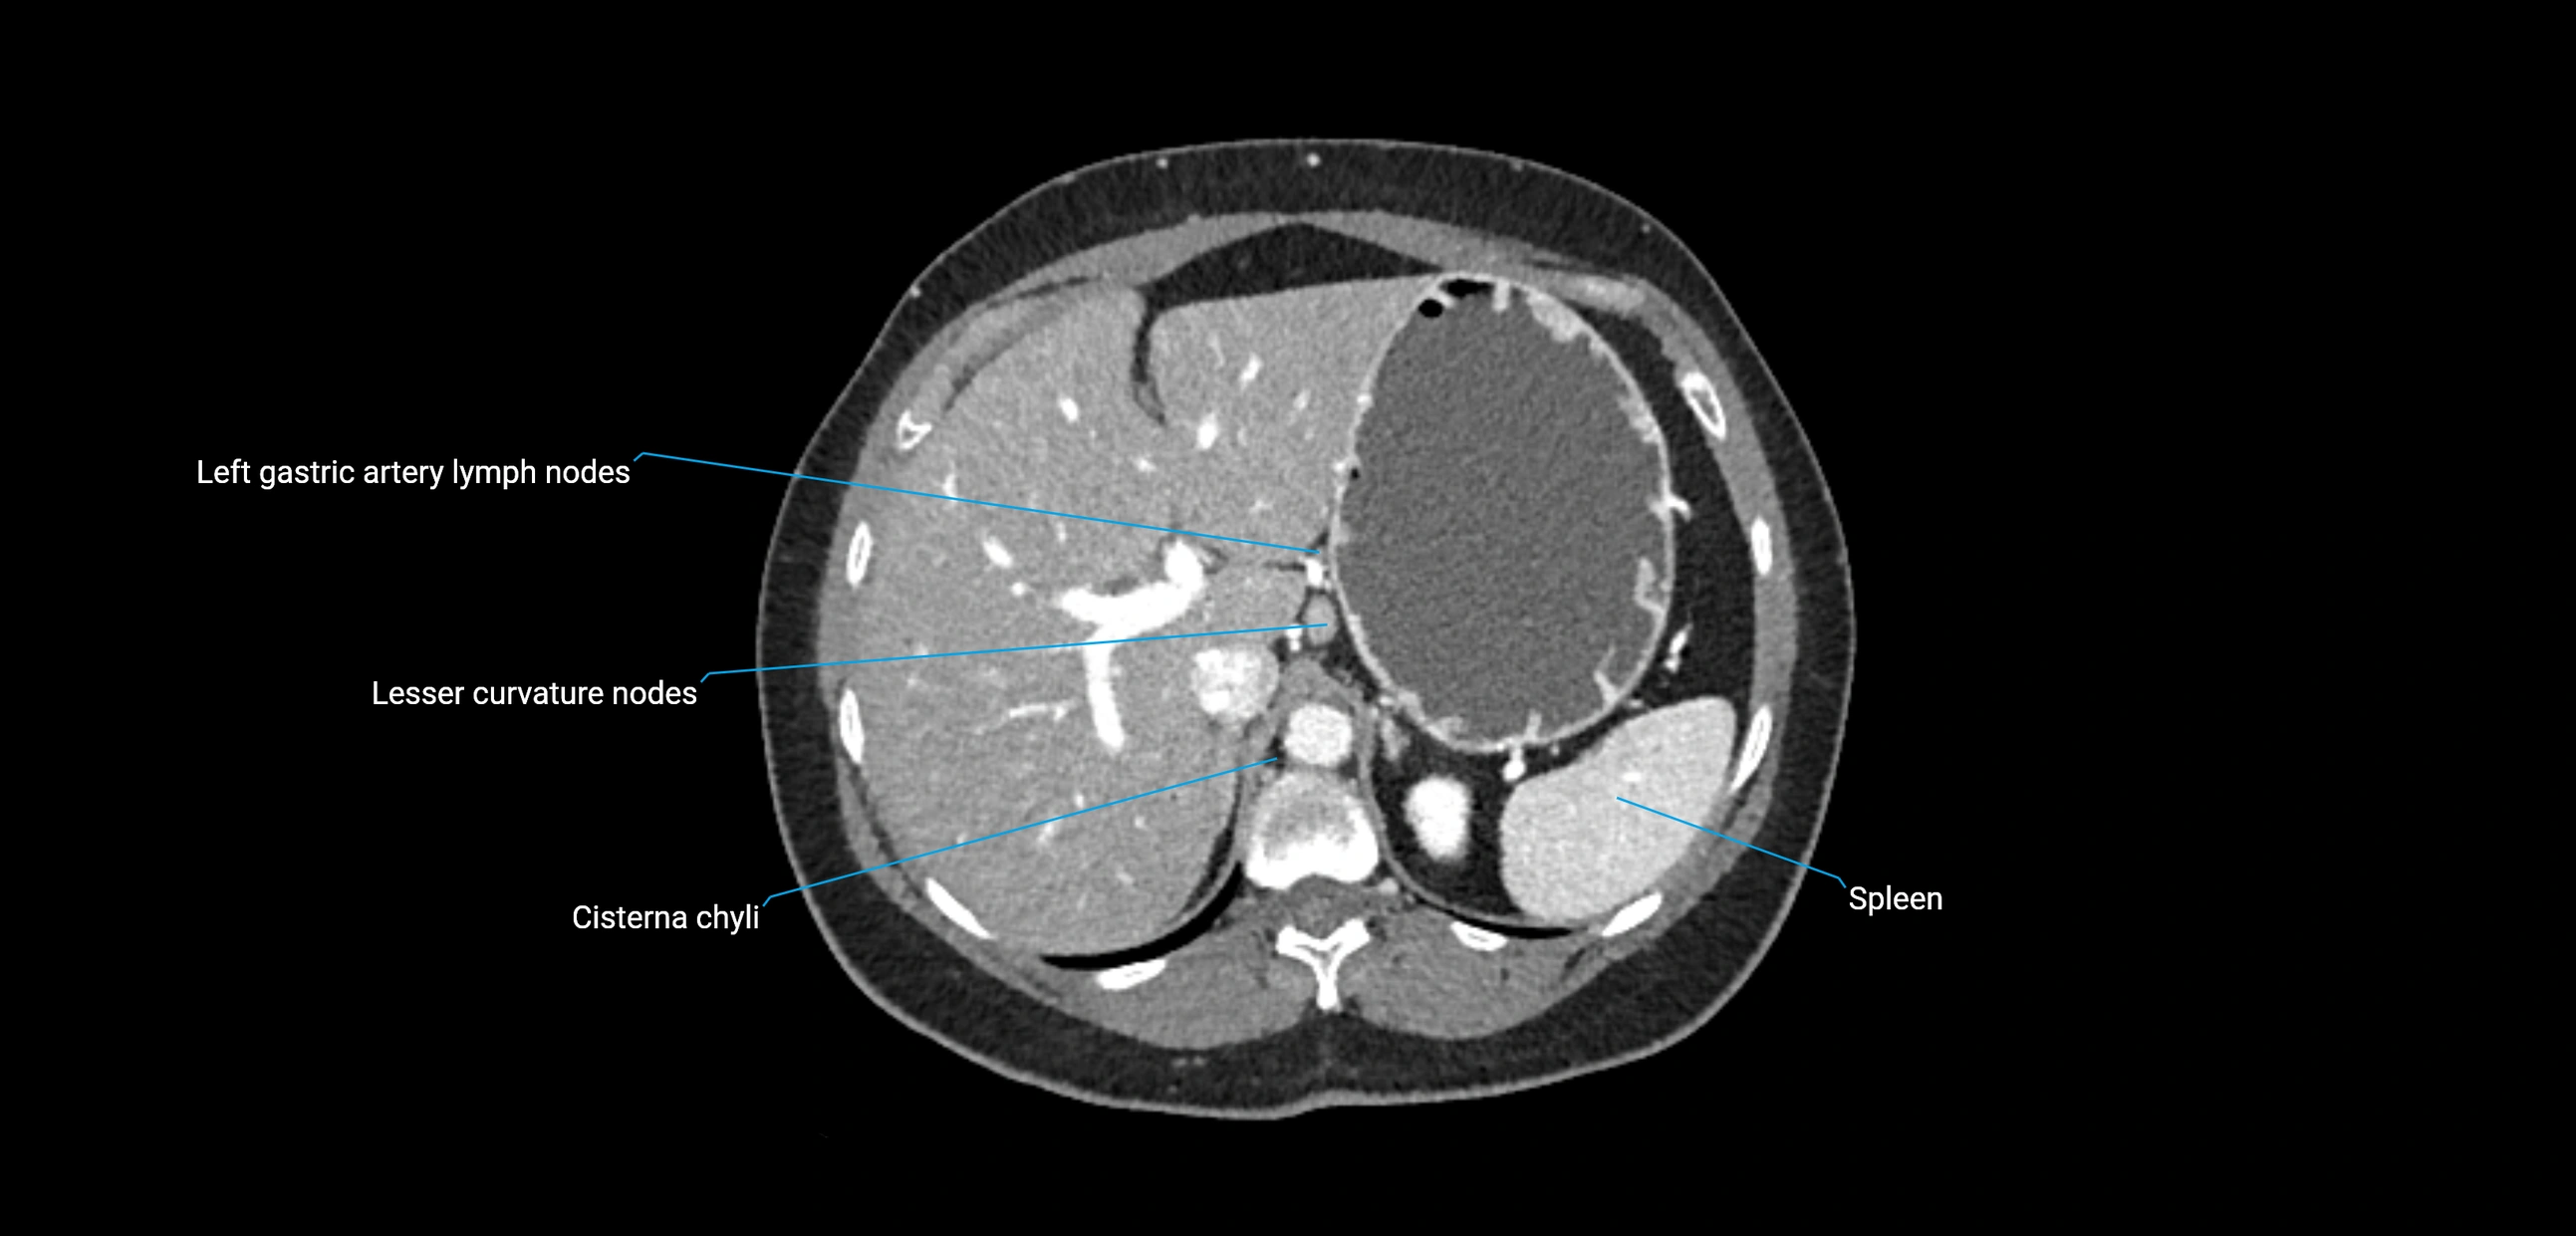

CT Appearance

CT Pre-Contrast:

• Nodes appear as soft-tissue density nodules adjacent to the aorta and IVC

• Calcification may be seen in chronic infections (e.g., tuberculosis)

CT Post-Contrast:

• Normal nodes enhance homogeneously

• Malignant nodes may show heterogeneous enhancement, central necrosis, or conglomerate formation

• Size >1 cm short axis is suspicious, though morphology and distribution are equally important

These nodes receive lymph from a wide range of abdominal and pelvic structures. Specifically, they drain lymph from the kidneys, suprarenal glands, gonads (testes/ovaries), uterus, uterine tubes, and pelvic organs, before converging into the lumbar lymphatic trunks, which terminate in the cisterna chyli → thoracic duct.